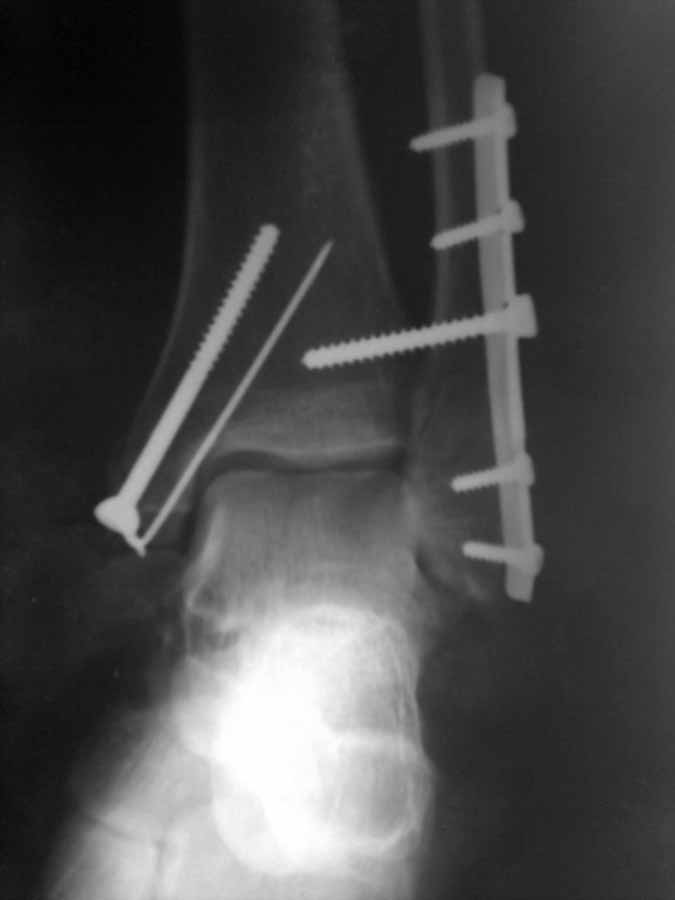

После операции высказали ряд замечаний. Не то что бы имею грандиозный опыт, но результат считаю достаточно удовлетворительным по крайней мере для того, что бы делать реМОС (так решило начальство.

Оцените обьективно ситуацию и проясните мне - это результат моей оплошности или предвзятое отношение